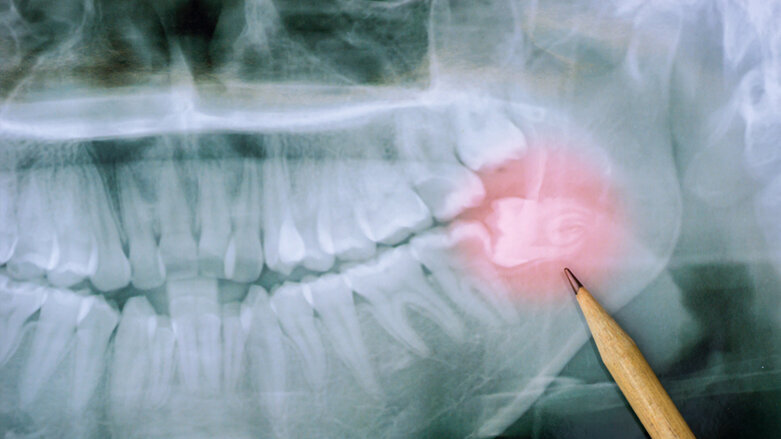

DÜSSELDORF - Die S2k-Leitlinie zur „Operativen Entfernung von Weisheitszähnen“ liegt jetzt in einer aktualisierten Fassung vor.

Die nach den Regularien der AWMF (Arbeitsgemeinschaft der Wissenschaftlichen Medizinischen Fachgesellschaften) erstellte S2k-Leitlinie zu dem häufigen Eingriff der Weisheitszahnentfernung ist aktualisiert worden.

Federführend durch die DGMKG und die DGZMK wurde in Zusammenarbeit mit sieben weiteren beteiligten Fachgesellschaften und Institutionen eine evidenz- und konsensbasierte Grundlage für die häufige und wichtige Therapieentscheidung zwischen dem Belassen und dem Entfernen von Weisheitszähnen erarbeitet. Die Leitlinie und den Methodenreport finden Sie hier.